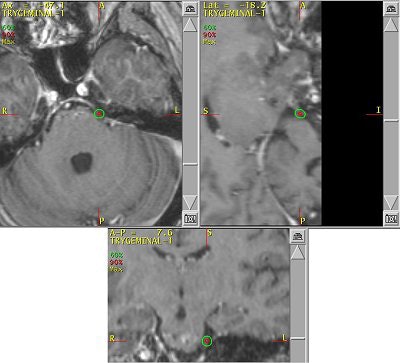

![]() |

| Proper alignment of patient and assembly is confirmed using lasers. Images courtesy of Dr. Kevin Murphy and University of California, San Diego, department of radiation oncology. |

Dr. Kevin Murphy, chief of stereotactic radiosurgery at the University of California, San Diego (UCSD), uses the Trilogy linear accelerator system from Varian Medical Systems of Palo Alto, CA. He describes its frameless head restraint as a mesh and plastic mask that is placed over the patient's face, then fastened to the table, preventing head motion. Other linear accelerator systems also utilize this type of head restraint.

The type of headgear used for TN treatment makes a big difference. "If you try to bolt someone's head, you can imagine that the V1 (nerve) through the forehead is activated and causes a lot of pain," explained Murphy. "And even if you bolt someone's head, they can still move. Any small muscle relaxation can drop that center off by 2 mm."